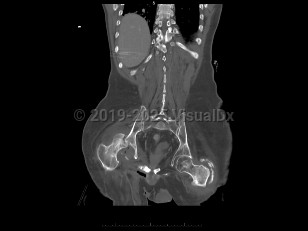

An infection of a joint most frequently caused by bacteria (although fungi, parasites, and mycobacteria may also rarely cause this infection).

This infection occurs most commonly as a result of hematogenous seeding of the joint in the setting of bacteremia. A joint may be inadvertently inoculated with a pathogen at the time of surgery or trauma. In some patients, a severe soft tissue infection may spread to involve a nearby joint.

Patients present with a swollen, warm, stiff, and painful joint. Fever may be present. The majority of the time, a single joint (usually the knee) is involved. Symptoms develop over 1-2 weeks. If the infection is caused by N gonorrhoeae, patients classically also present with a rash and tenosynovitis. If the infection is due to fungi or mycobacteria, the symptoms may be subtler and may worsen more gradually.

Diagnosis can be made by arthrocentesis. Joint fluid should be sent for analysis including cell count, microscopic analysis for crystals, Gram stain, and bacterial culture. Additional cultures of the joint fluid can be obtained if an atypical pathogen is suspected by history or examination.